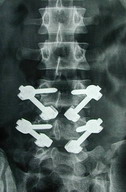

治療關於頸椎椎弓裂的治療應根據臨床症狀、滑脫的程度以及是否合併脊髓、神經根損害來決定選擇適當的治療方式。對於無明顯臨床症狀者,應加強對頸部的保護及注意日常工作、生活時的體位。一旦出現神經根或脊髓損害症狀或伴有滑脫,我們認為應考慮外科手術干預。手術的目的在於:(1)減壓,改善臨床症狀。(2)融合,使病變節段獲得牢固穩定。手術應選擇經前路途徑,將椎弓裂椎節與下位椎節相融合。如下伴滑脫,可採用環鋸法或椎間盤切除減壓與自體髂骨植骨術,對於合併頸椎滑脫者,我們採用 Caspar椎體牽開器,使滑脫之椎節復位,椎間孔擴大,恢復頸椎椎間高度及生理曲度,然後再行減壓及植骨。如條件允許,植骨後還可輔以頸椎帶鎖鋼板內固定,使融合節段達到即刻穩定,這樣可免除術後石膏外固定,減輕了患者痛苦。

後路手術也可進行植骨融合,使頸椎椎弓裂椎節獲得穩定,但與前路手術相比後路手術存在如下缺點:(1)手術創傷大,出血量多。(2)無法進行直接減壓,特別是椎間隙處的減壓,且難以恢復頸椎椎間高度及生理曲度。(3)對合併滑脫的病例使其達到良好的復位較為困難。(4)後路植骨融合範圍較大,影響頸部運動功能。(5)若採用內固定,手術難度大,危險性高。因此,除非患者合併椎管狹窄可考慮後路手術外,一般應選擇前路手術。